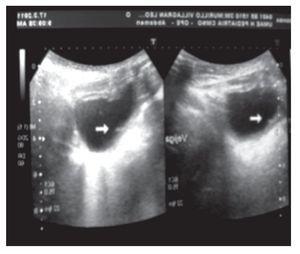

Fue recibido en el Instituto a los cinco meses de edad, durante esta visita se realizó ultrasonido renal y vesical, observando un gran divertículo vesical a la izquierda de la vejiga, cuyo tamaño era de dimensiones similares a la vejiga (Figura 1). La uretrocistografía confirmó el hallazgo del ultrasonido (Figura 2).

Figura 1.Ultrasonido con evidencia del divertículo proveniente de vejiga, con cuello de divertículo ubicado en piso vesical.